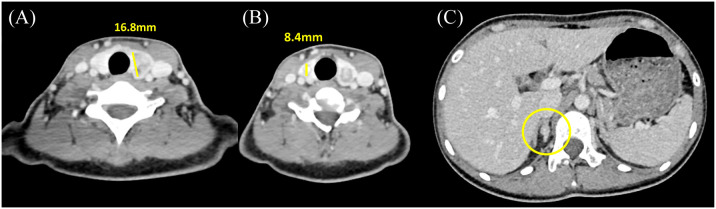

Multiple endocrine neoplasia type 2B (MEN2B) is a rare autosomal dominant disorder caused by germline pathogenic RET variants. On the other hand, Charcot-Marie-Tooth disease (CMT) is a hereditary neurological disorder, characterized by distal muscle weakness and sensory loss, with approximately 100 identified causative genes. Herein, we report a de novo RET mutation in a patient presenting with clinical features of both MEN2B and CMT. The patient, a 22-year-old woman, had a history of lower limb muscle weakness, with no family history of MEN2B or CMT. The patient was being treated for a thyroid gland neoplasm. Genetic testing of the medullary thyroid carcinoma revealed a previously unreported RET germline variant, p.M918W (RET: c.2752_2753delinsTG, p.Met918Trp). The novel p.M918W RET variant was associated with concurrent MEN2B and CMT. This finding was unexpected as MEN2B typically manifests with distinct features, such as marfanoid habitus and mucosal neuromas, but not with muscle weakness, as seen in CMT. Based on this finding, the plausible role of the p.M918W mutation as a shared pathway for both MEN2B and CMT warrants further investigation.